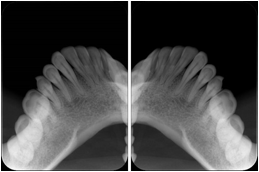

3. A patient in rural Minnesota experiences sudden vision loss and goes to a general ophthalmologist, who acquires OCT images and forwards them electronically along with a Structured Display to a retina specialist six travel hours away. The retina specialist is able to view the images in the standard layout that he is comfortable with, and to confirm that the patient has a choroidal neovascular membrane. He determines that is would be worthwhile for the patient to travel for treatment.

OCT Retinal Study with Cross Section and Navigation Structured Display

Figure OO-4. OCT Retinal Study with Cross Section and Navigation Structured Display